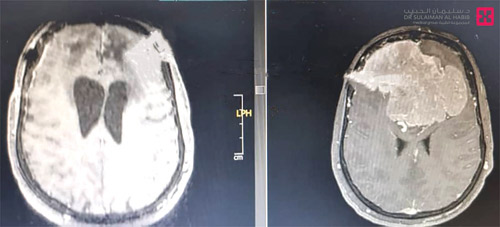

أنهى فريق طبي متخصص بمستشفى الدكتور سليمان الحبيب بالقصيم، معاناة امرأة خمسينية، مصابة بورم دماغي كبير، ضاغط على العصب البصري من الجهتين وكذلك عصب الشم، وتسبب في إثارة الكثير من الأعراض الحادة، التي نغصت حياتها لفترة طويلة، ذكر ذلك د.ناجي مسعود استشاري جراحة المخ والأعصاب والعمود الفقري، رئيس الفريق الطبي المعالج. وقال د.مسعود إن المريضة راجعت المستشفى بعد رحلة بحث عن العلاج مضنية، شملت عدة مستشفيات بالقصيم والرياض، لكن الأطباء فيها اعتذروا لها تخوفاً من المضاعفات التي قد تنجم عن التدخل الجراحي، وقد كانت تشتكي من حزمة أعراض حادة أبرزها ضعف نظر يصل إلى 70% في العين اليسرى و30% في اليمنى، وفقدان كامل لحاسة الشم، بالإضافة إلى الصداع المزمن والدوخة. وتابع مسعود قائلاً إن المريضة فور وصولها خضعت لعدة فحوصات دقيقة، منها الرنين المغناطيسي MRI بالصبغة وبدونها، والأشعة المقطعية CT Scan، وقد أظهرت الصور الطبية وجود ورم دماغي ضخم ضاغط على العصب البصري من الجهتين، وكذلك على عصب الشم، وبعد دراسة الحالة وفقاً لنتائج الفحوصات، خلص الفريق الطبي إلى أن التدخل الجراحي هو السبيل الأمثل للتعامل مع الحالة، وبعد اتخاذ كافة الترتيبات والتحضيرات اللازمة خضعت المريضة لعملية دقيقة، تم فيها إزالة الورم بشكل كامل، باستخدام الميكروسكوب pantero، ومراقبة الأعصاب الحركية والاحساس، وبفضل الله نجحت العملية التي استمرت لـ»7» ساعات بشكل متكامل، وبدأت حالة المريضة في التحسن على نحو متسارع بعد العملية، وطوال فترة التنويم التي استمرت لنحو أسبوعين، إذ غادرت بعدها المستشفى بحالة صحية جيدة، وقبل ذلك خضعت لفحص نظر والذي أكدت نتائجه أنها استعادت النظر في العين اليسرى بنسبة تجاوزت 80% وفي اليسرى بـ 95%، بالإضافة إلى أنها استعادت حاسة الشم بنسبة تجاوزت أيضاً 95%، كما تخلصت من كافة الأعراض الأخرى بشكل كامل، وقد راجعت العيادة بعد خروجها من المستشفى عدة مرات ولم تشتك من شيء. الجدير بالذكر أن مستشفى الدكتور سليمان الحبيب بالقصيم إضافة مهمة للقطاع الصحي بالمنطقة، ويمثل نقلة نوعية في الرعاية الصحية التي يحظى بها أبناؤها، لاعتماده على أفضل الكوادر الطبية وأميزها في مختلف التخصصات، وتوظيفه لأحدث وأفضل ما أنتجته التكنولوجيا الطبية من الأجهزة التشخيصية والعلاجية.